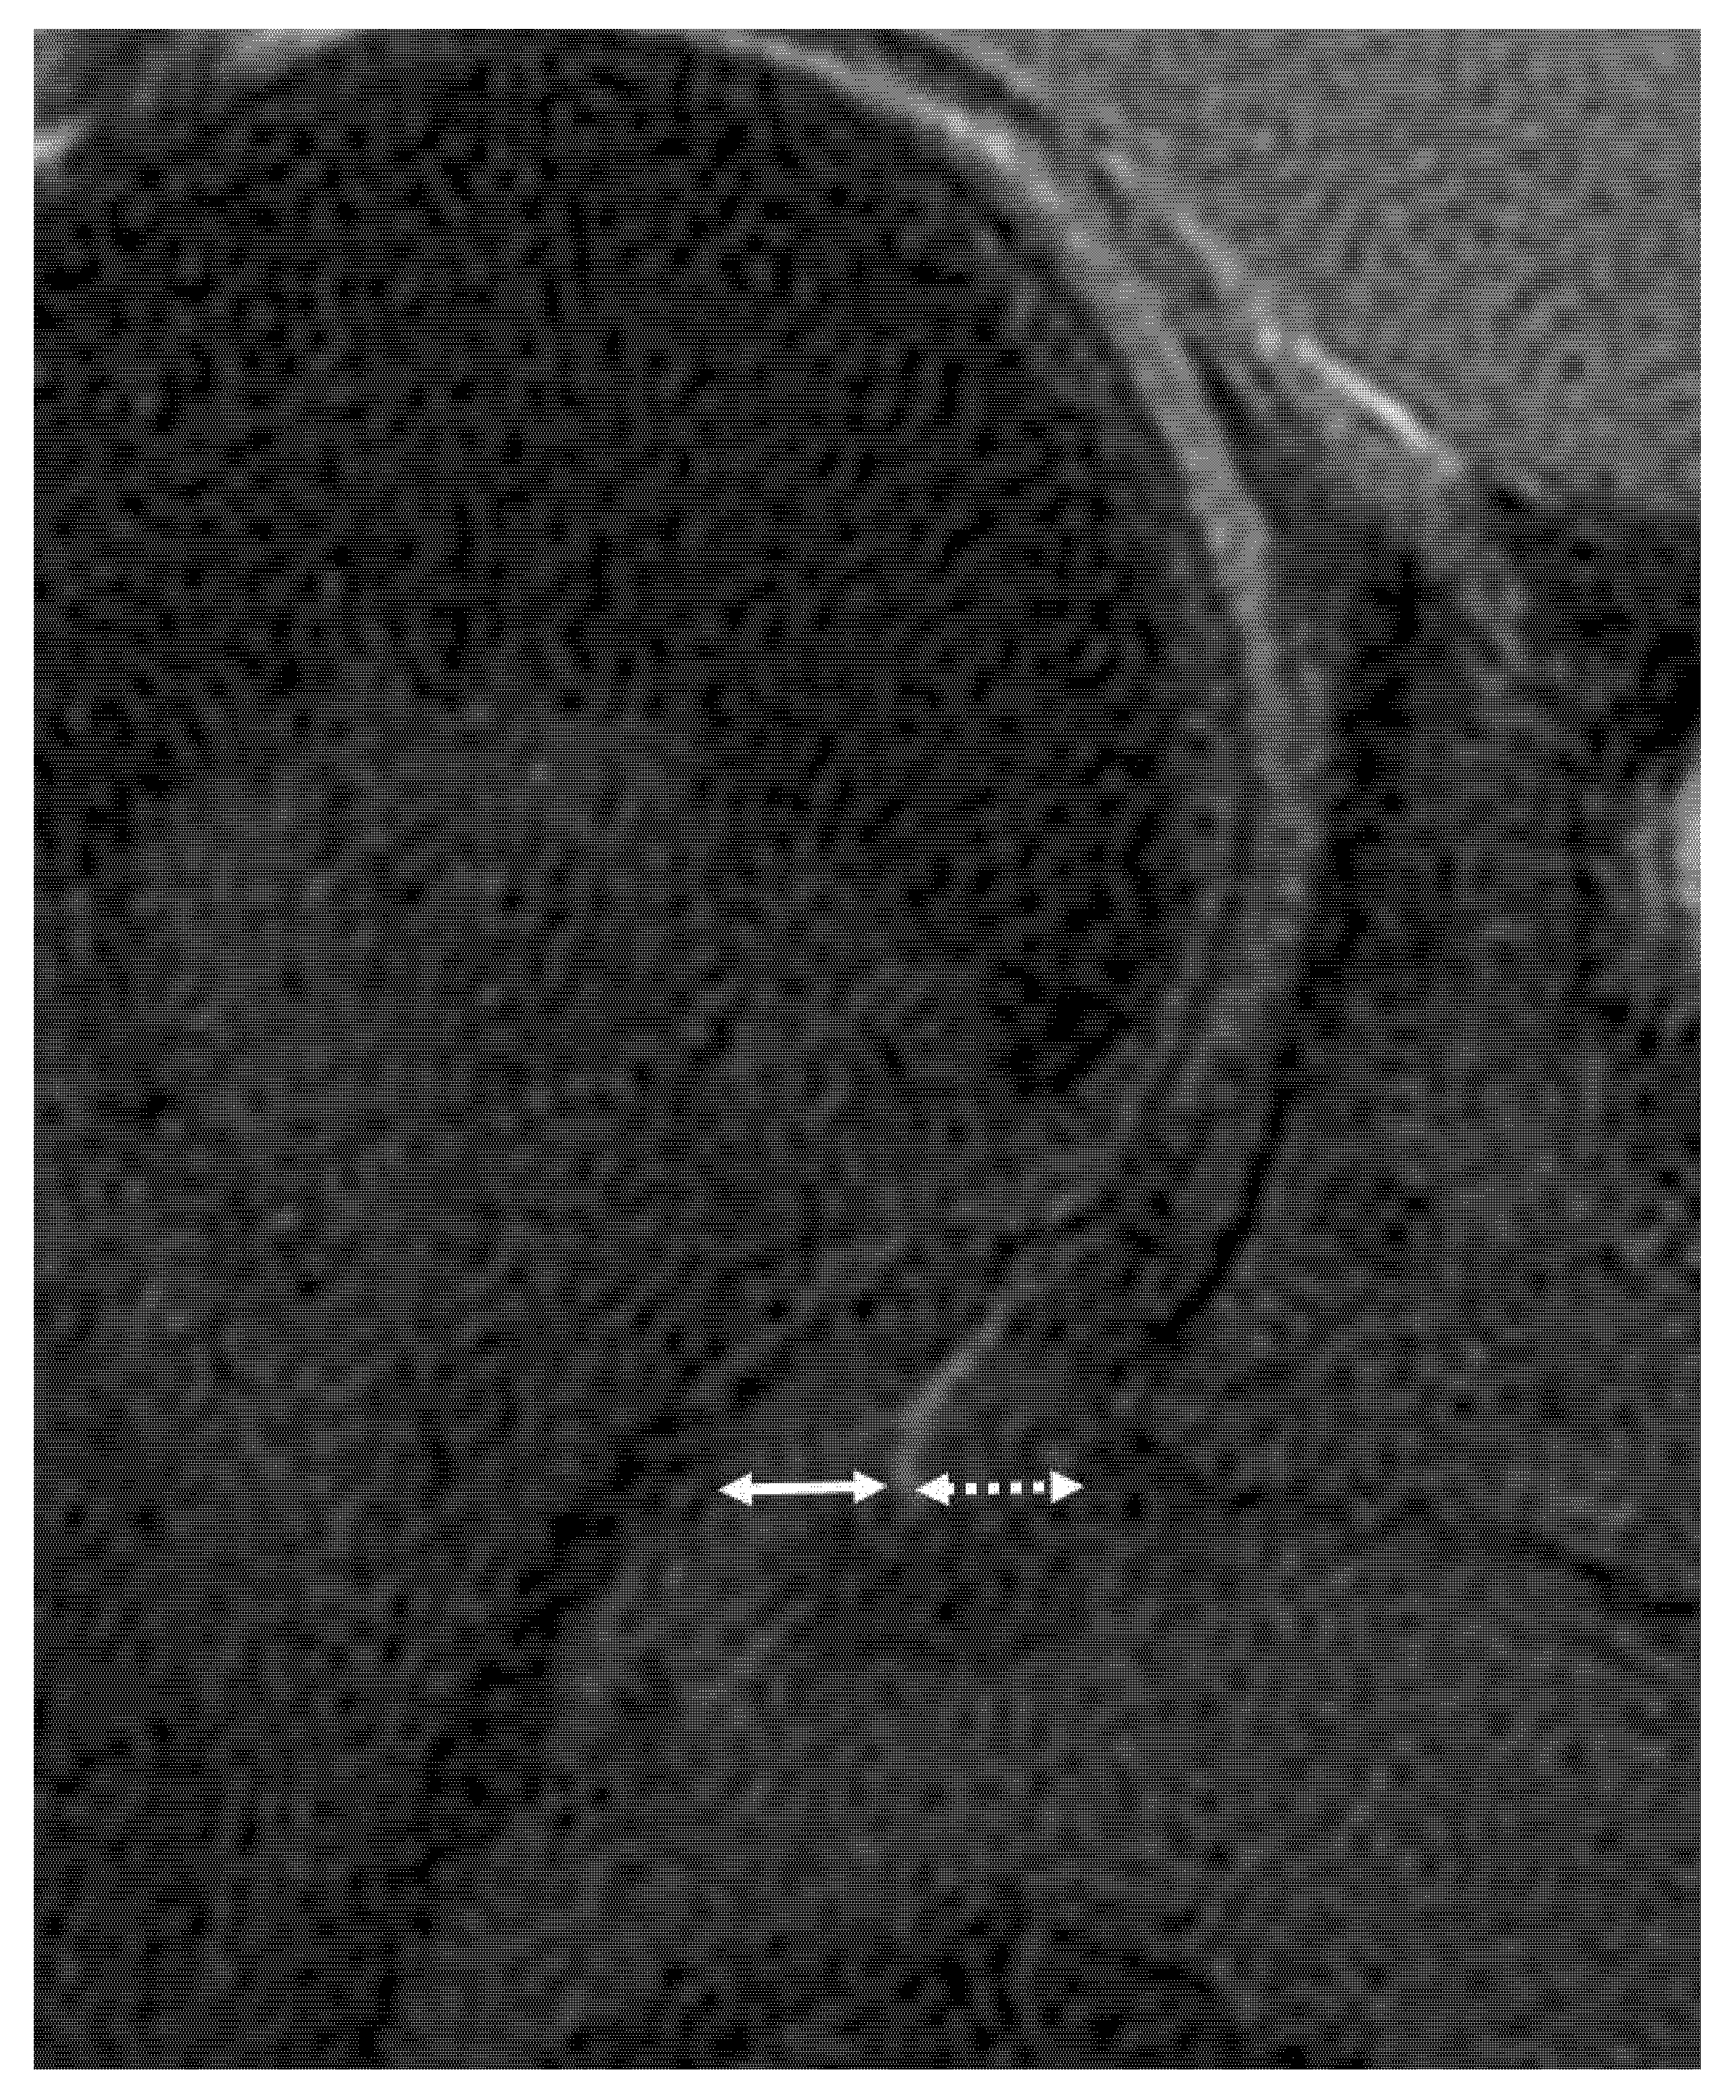

From www.indianradiology.com

Adhesive Capsulitis MRI Sumer's Radiology Blog Adhesive Capsulitis Tests And Measures Adhesive capsulitis, also known as frozen shoulder, is an inflammatory condition characterized by shoulder stiffness and pain. Adhesive capsulitis is diagnosed by numerous physical characteristics including a thickening of the synovial capsule, adhesions. Adhesive capsulitis, also known as frozen shoulder, is a condition characterized by pain and significant loss of both active range of motion (arom) and passive range of. Adhesive Capsulitis Tests And Measures.

Adhesive Capsulitis MRI Sumer's Radiology Blog Adhesive Capsulitis Tests And Measures Adhesive capsulitis, also known as frozen shoulder, is a condition characterized by pain and significant loss of both active range of motion (arom) and passive range of motion. Adhesive capsulitis is characterized by a painful, gradual loss of both active and passive glenohumeral motion in multiple planes. Adhesive capsulitis, also known as frozen shoulder, is an inflammatory condition characterized by. Adhesive Capsulitis Tests And Measures.

From www.sportsmedreview.com

MRI Findings in Adhesive Capsulitis of the Shoulder Sports Medicine Adhesive Capsulitis Tests And Measures Symptoms usually start slowly and get worse over time. Adhesive capsulitis, also known as frozen shoulder, is a condition characterized by pain and significant loss of both active range of motion (arom) and passive range of motion. Adhesive capsulitis, also known as frozen shoulder, is an inflammatory condition characterized by shoulder stiffness and pain. Adhesive capsulitis is diagnosed by numerous. Adhesive Capsulitis Tests And Measures.